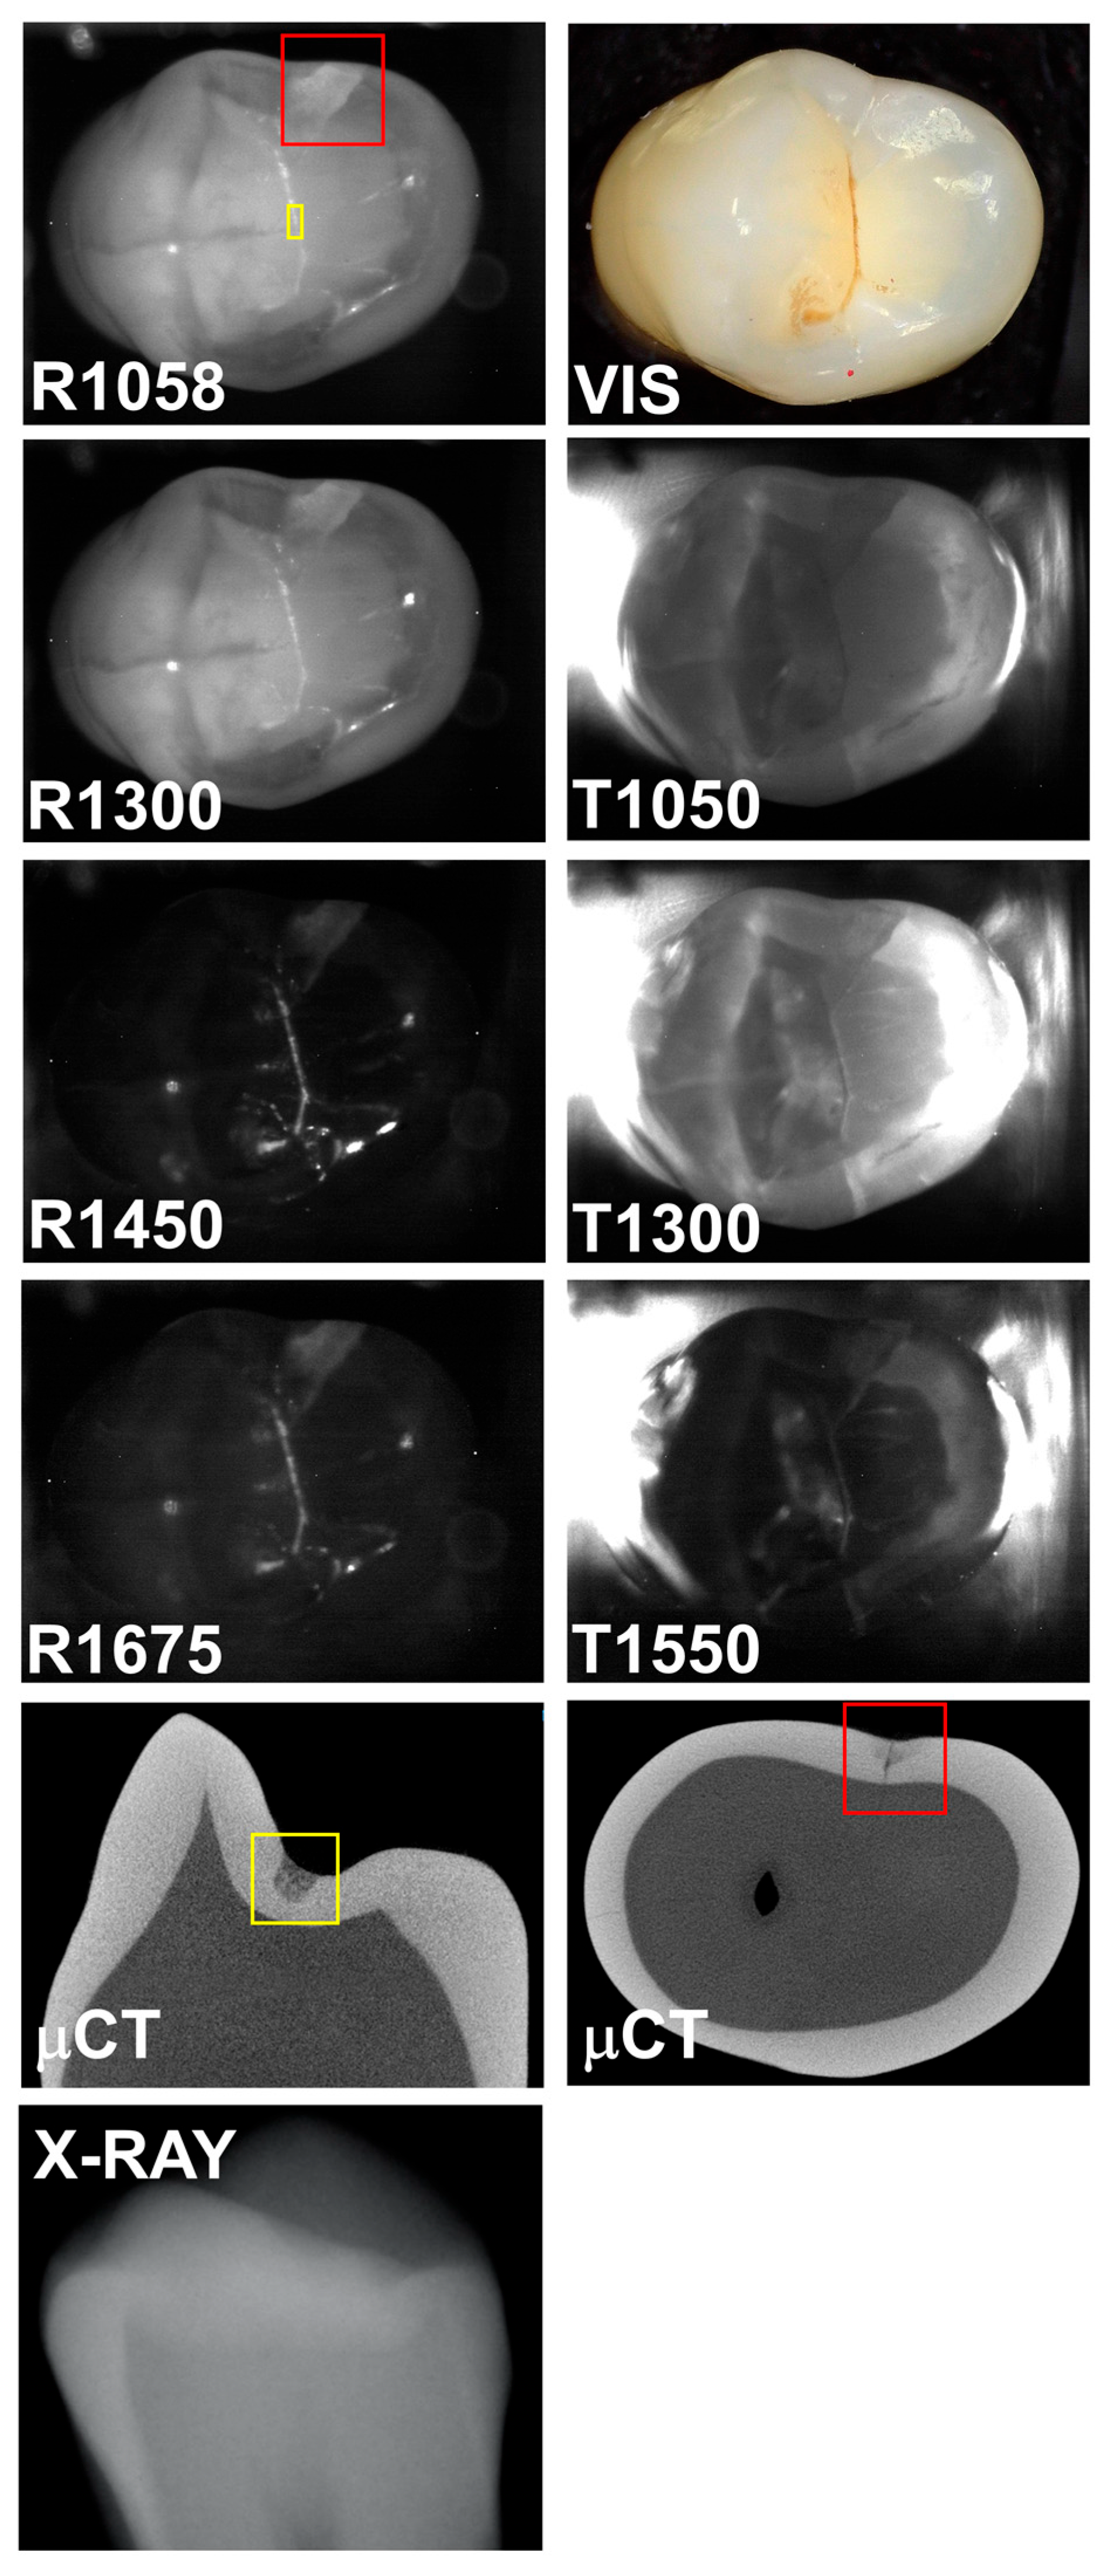

A third tooth with both occlusal and interproximal lesions is shown in Figure 4. The interproximal lesion can be seen in the μCT image and all the SWIR images; however, it is not visible in the color image or the radiograph. The interproximal lesion is visible in all the SWIR reflectance images with high contrasts of 0.43, 0.32, 0.58, and 0.56 at 1058, 1300, 1450, and 1675 nm, respectively. However, the contrasts were 0.26, 0.22, and −0.03 for transillumination at 1050, 1300, and 1550 nm. The contrast becomes inverted at 1550 nm, and the lesion area appears brighter than the surrounding sound area for transillumination. The same phenomenon occurs for the occlusal decay in the fissure. The occlusal decay in the fissure is visible with high contrast in the 1450 and 1675 nm images with contrasts of 0.79 and 0.67, respectively, at the position indicated by the yellow box. The contrasts are much lower at 1058 and 1300 nm with values of 0.18 and 0.2, respectively. The contrasts for transillumination were 0.15, 0.10, and −0.28 at 1050, 1300, and 1550 nm. Again, the contrast is inverted for transillumination at 1550 nm.

Figure 4. SWIR occlusal reflectance (R) images at 1058, 1300, 1450, and 1675 nm along with SWIR occlusal transillumination (T) images at 1050, 1300, and 1550 nm are shown for a tooth with an occlusal lesion (yellow box) and an interproximal lesion (red box). A color (VIS) image, two slices extracted from the μCT image, and a radiograph (X-RAY) are also shown.

Reflectance at 1058 nm and 1300 nm was also included because it is also desirable to better visualize the surface of the tooth, and at longer wavelengths beyond 1400 nm the surface of sound areas of the tooth may not be visible due to the lower scattering of sound enamel and the increase in water absorption [4]. This is particularly challenging when surfaces are wet. Time-resolved SWIR reflectance imaging during the drying of lesions with forced air can be used to assess the activity of lesions [4], and it may be difficult to view the lesions to optimally position the imaging probe directly over the lesions being investigated. The use of a second reflectance wavelength may greatly aid alignment. In addition, image registration of the sequential images may benefit from the higher reflectivity, particularly at 1058 nm. The reflectance images shown in Figure 2, Figure 3 and Figure 4 clearly show the increased visibility of sound areas of the tooth compared to 1450 and 1675 nm.